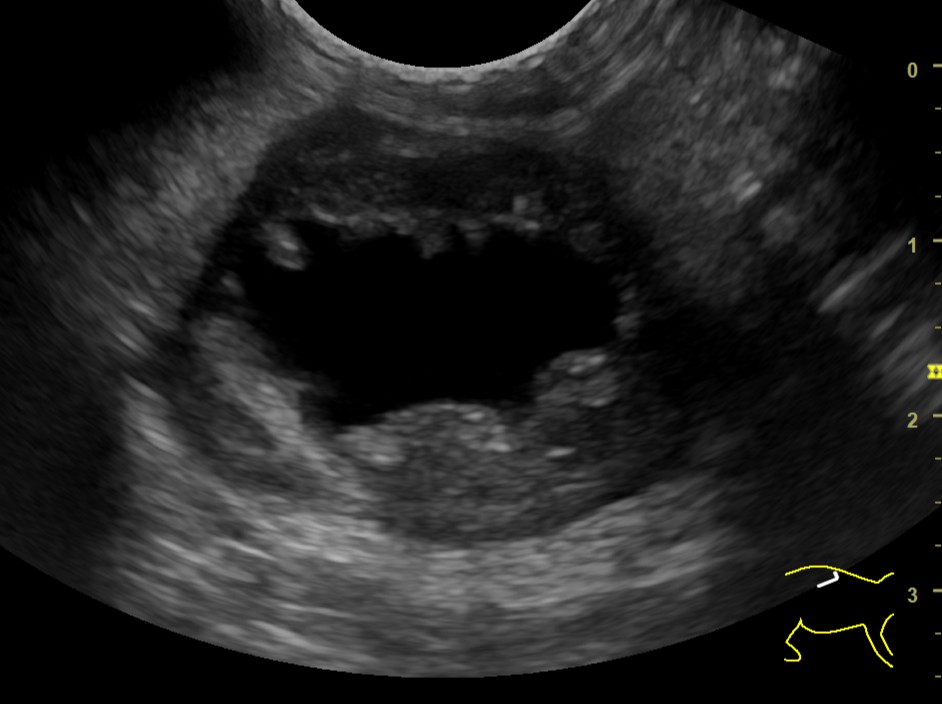

腹部超音波検査

膀胱や腎臓の内部構造をリアルタイムで観察できます。腫瘍や結石、腎臓の構造異常の早期発見に役立ちます。